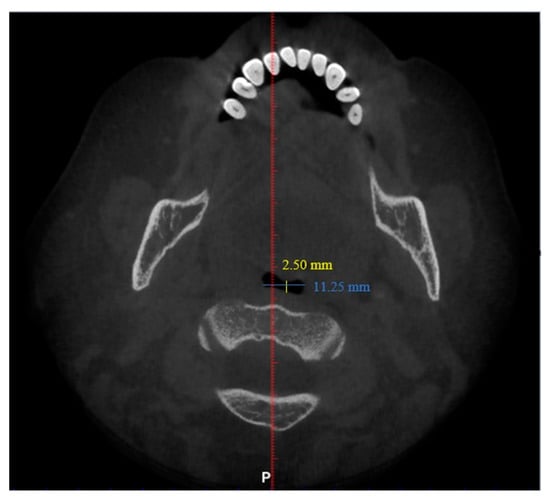

| Antero-posterior (mm) | 101 | 1.00 | 14.50 | 6.44 | 3.19 |

| Width (mm) | 101 | 8.00 | 37.00 | 21.69 | 6.54 |